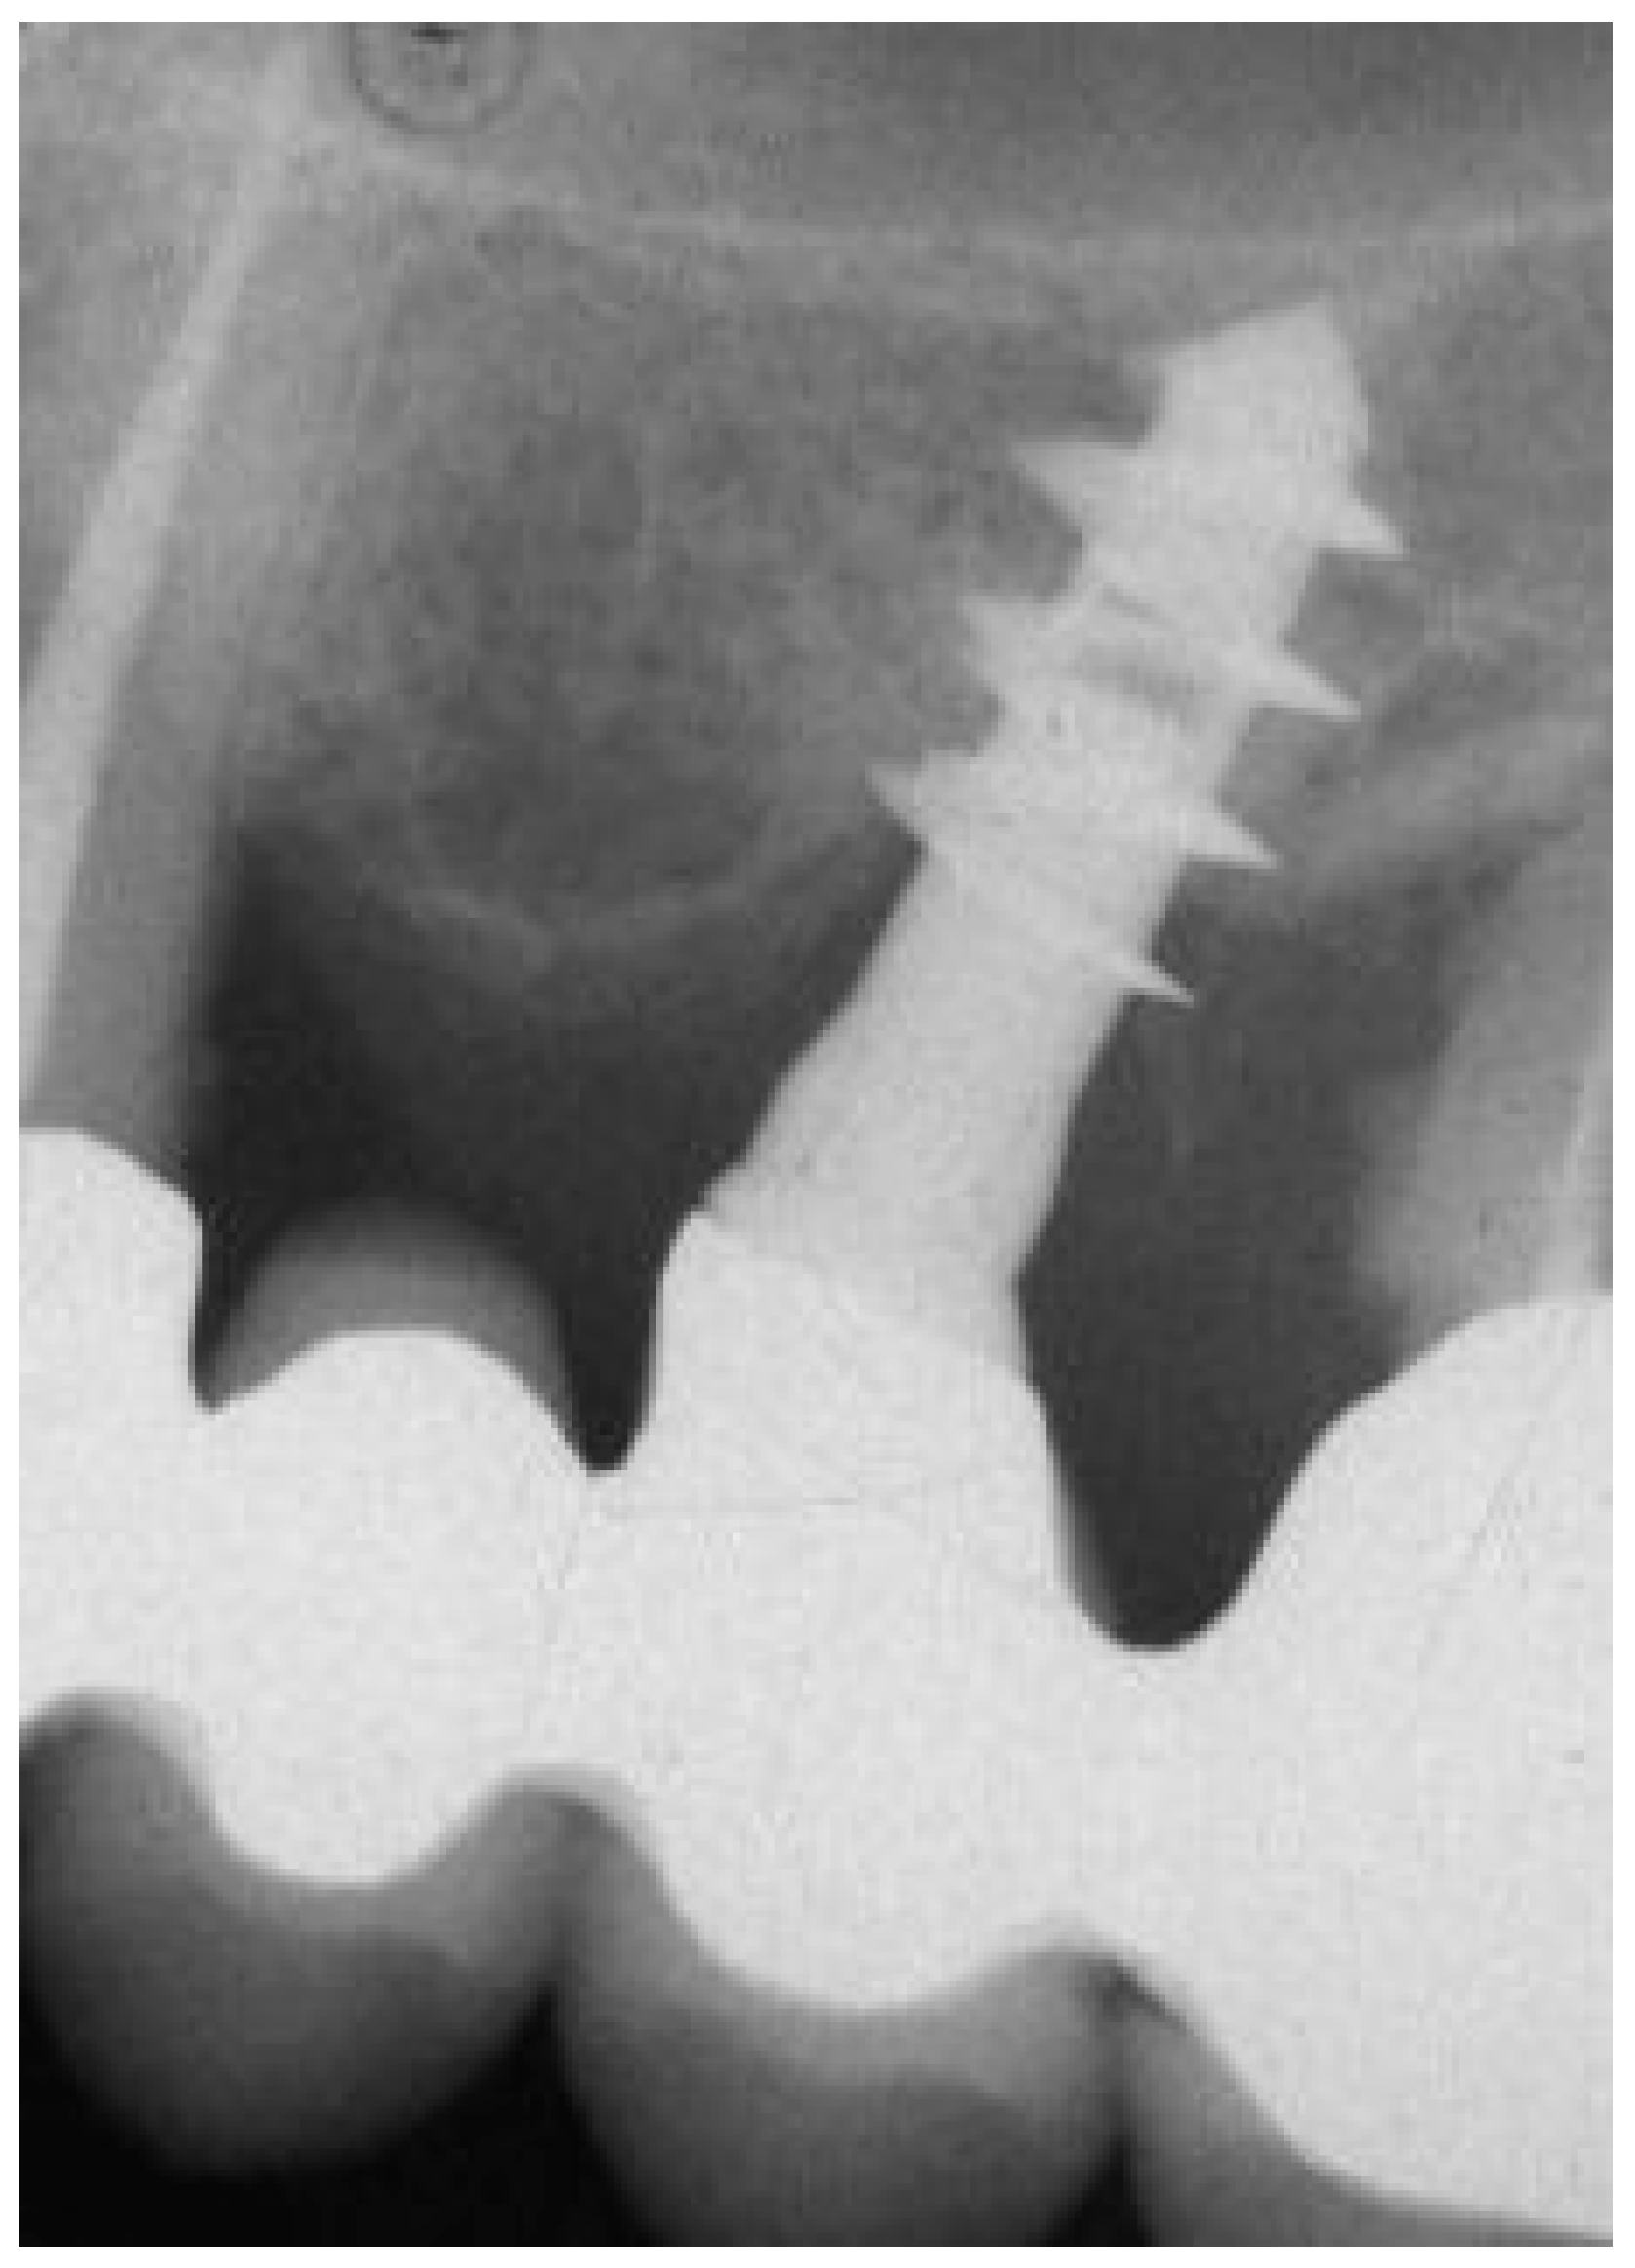

The actual length of the implant was measured at 12 mm and was used for radiographical calibration. The length originally in bone contact, measured from the top edge of the implant to its tip, was 11 mm. Bone loss was calculated from the calibrated radiograph as the distance between the marginal bone level and the implant apex, totaling 3.5 mm. Importantly, despite the presence of bone pockets surrounding the first thread, due to severe periodontitis affecting neighboring teeth, pre-removal periapical X-rays (Figure 1) also indicated consistent osseointegration of the implant, which was subsequently measured using histological techniques.

Figure 1.

Periapical X-ray before implant retrieval.